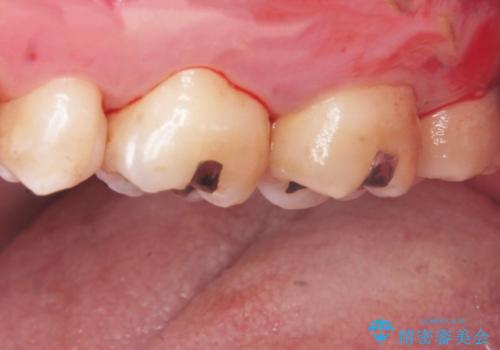

3. 縁下歯石のクリーニングの治療後